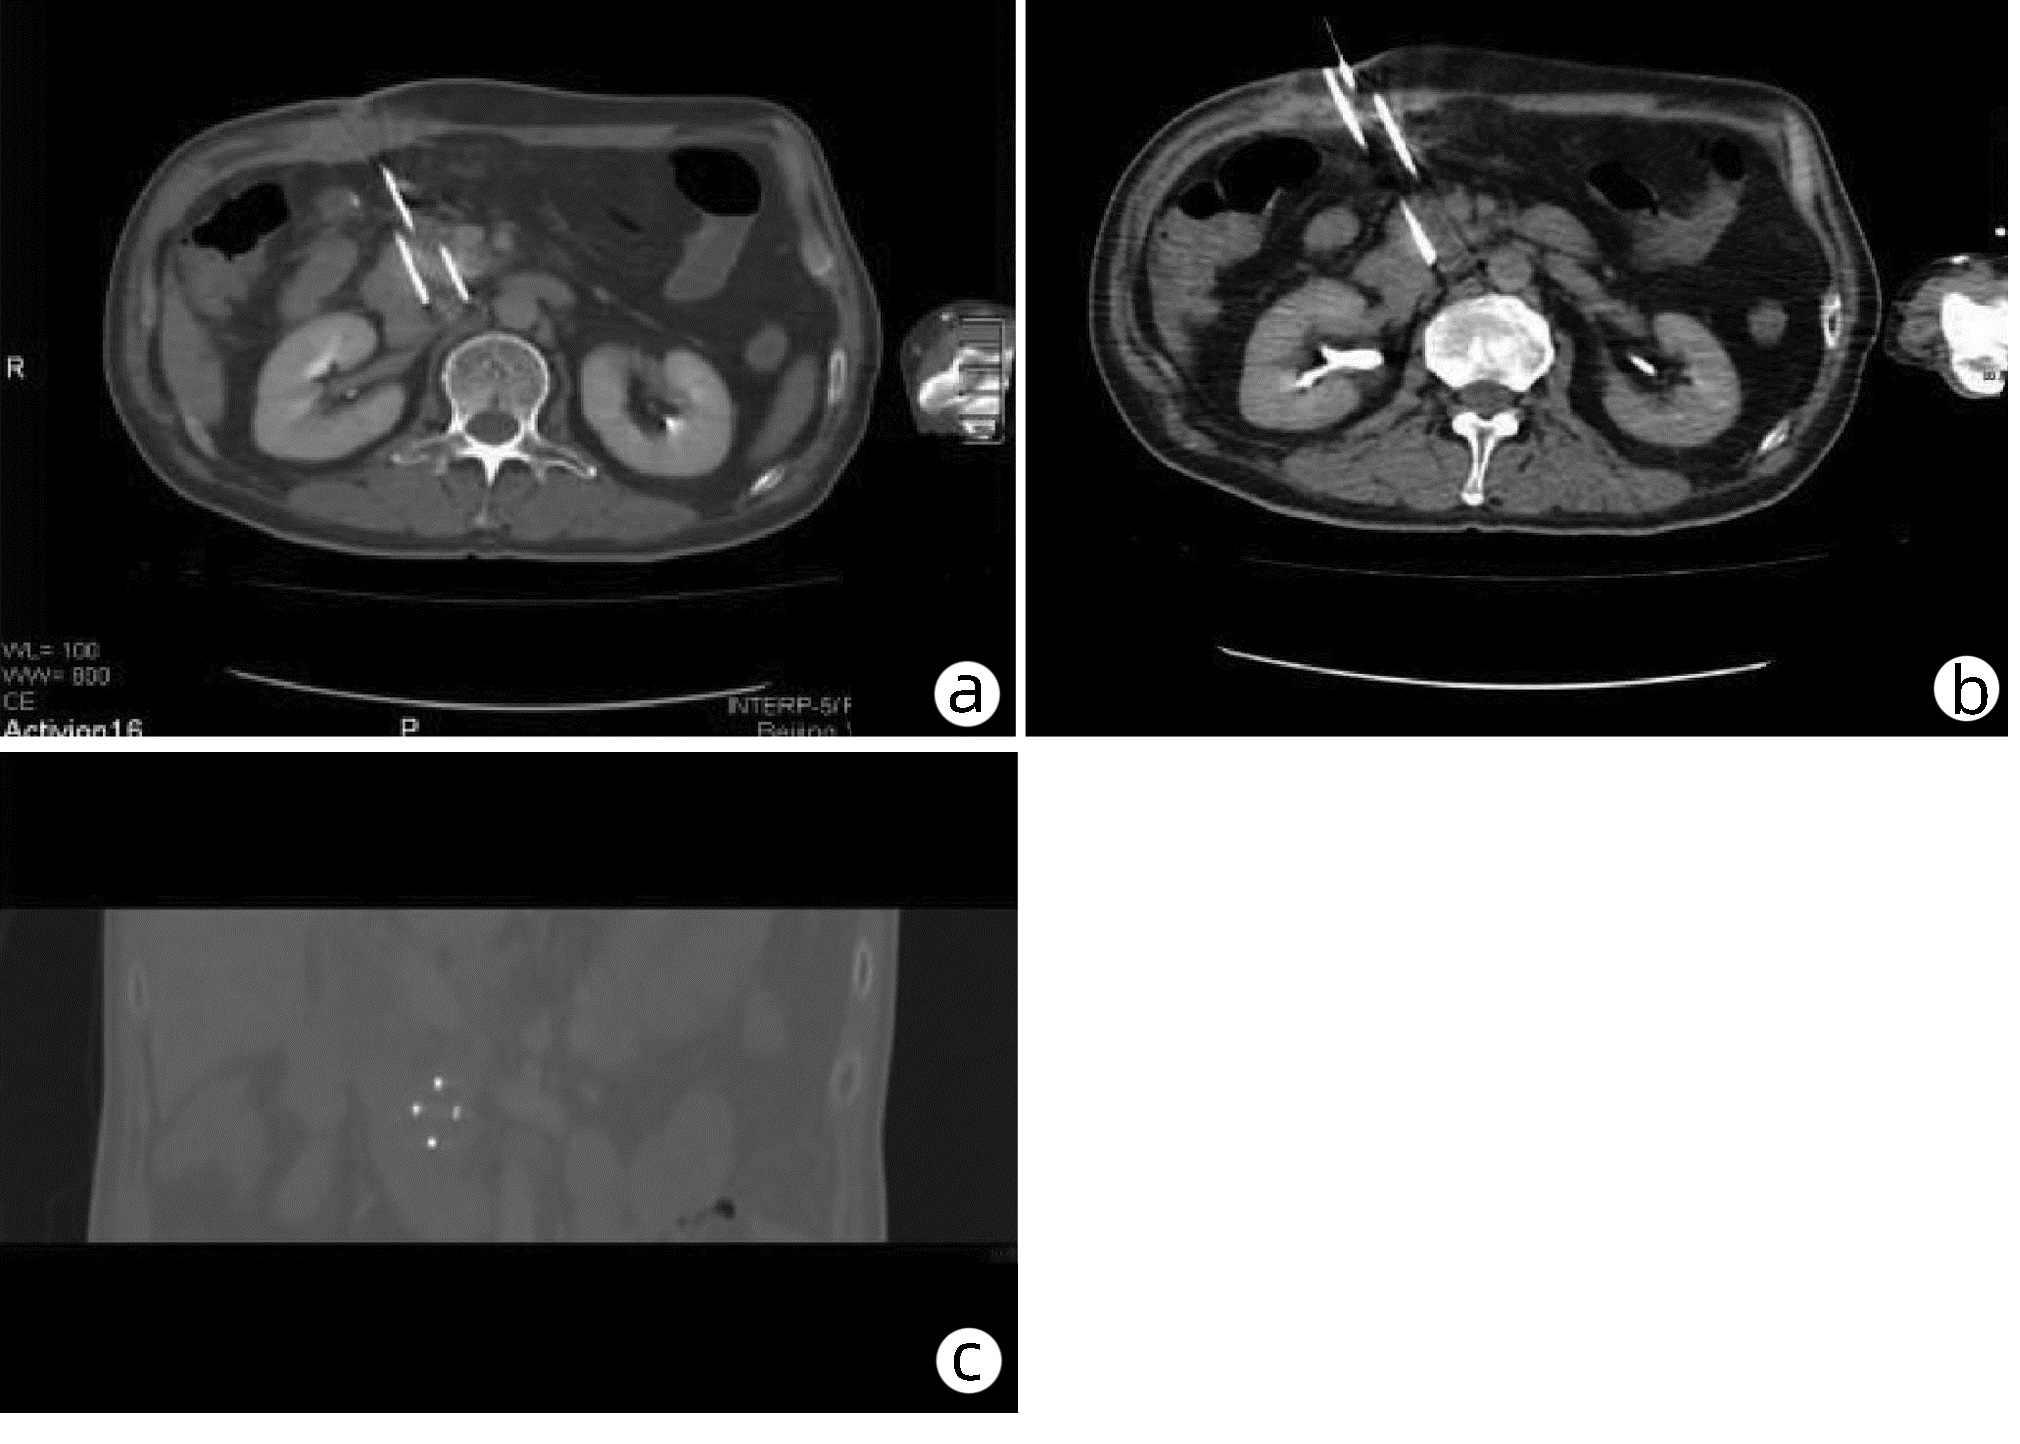

Relationship between visceral fat related index and the severity of acute pancreatitis

Heming HUANG, Huiying YANG, Yingying QIN, Guodu TANG

2022, 38(10): 2313-2319. DOI: 10.3969/j.issn.1001-5256.2022.10.021

Abstract(987) HTML (347) PDF (2160KB)(97)

Abstract:

Objective  To investigate the relationship between visceral fat related index and the severity of acute pancreatitis (AP).  Methods  A total of 308 patients hospitalized with AP at the First Affiliated Hospital of Guangxi Medical University from September 2014 to October 2021 were included. They were divided into mild acute pancreatitis (MAP) (n=186), moderate severe acute pancreatitis (MSAP) (n=60) and severe acute pancreatitis (SAP) (n=62) for comparison in age, hospitalization cost and days, scoring systems and body mass indexes. Comparison of normally distributed continuous data with homogeneity of variance between groups was made by one-way analysis of variance, and intergroup and intragroup pairwise comparison of data with heterogeneity of variance was made by the Kruskal-Wallis H test. The receiver operating characteristic curves (ROCs) for each index were constructed and area under the curve (AUC) was calculated to evaluate the performance of each index. Univariable and multivariable logistic regression analyses were used to identify the independent risk factors of MSAP and SAP.  Results  There were significant differences among the three groups in terms of hospitalization costs and durations, TG, HDL-C, NLR, WBC, Alb, Cr, BUN, scoring systems, CMI, LAP, WTI and CVAI. Further pairwise comparisons revealed that CMI, LAP, WTI and CVAI were significantly higher in the MAP group than in MSAP and SAP groups. We also found correlation between CMI and the severity of AP (r=0.352, P < 0.001). By comparing the AUCs, CMI was found to be the most accurate in predicting the occurrence of MSAP and SAP. Univariable logistic regression analysis showed that CMI, LAP, WTI, CVAI and WC were the risk factors of MSAP and SAP. After adjusting for confounding factors, CMI and CVAI were identified as the independent risk factors of MSAP and SAP. The risk of MSAP and SAP with CMI ≥ 0.801 was 3.740 times that with CMI < 0.801 (95%CI: 1.983~7.056, P < 0.001).  Conclusions  Visceral fat is related to the severity of AP. Among the four visceral fat related indexes (CMI, LAP, WTI and CVAI), cardiometabolic index is the most valuable in predicting the severity of AP and they are positively correlated. CMI, an independent risk factor for MSAP and SAP, can be used to predict and assess the severity of AP.